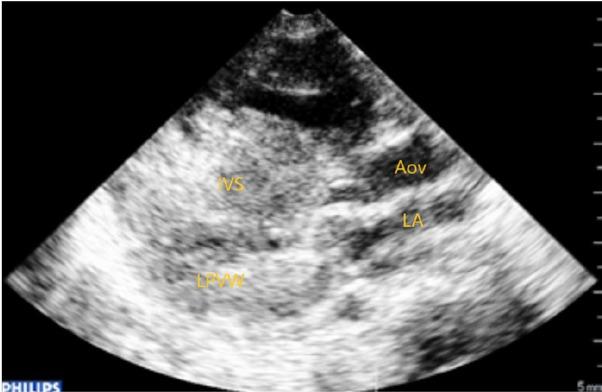

2D, color and continuous-wave Doppler echocardiography showed obstructive hypertrophic cardiomyopathy (OHCM) predominantly in the septal region (Fig. 2, 3), pulmonary infundibular and valvular stenosis as well as a small ASD with a left to right shunt.

Transthoracic echocardiography parasternal long axis view: hypertrophic cardiomyopathy predominantly septal (IVS-interventricular septum, LPW-left posterior ventricular wall, LA-left atrium, AoV-aortic valve)